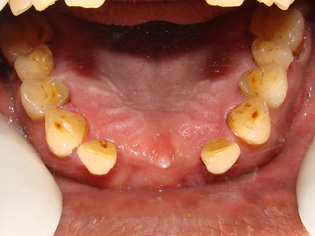

病例上颌前牙缺失

患者,黄某。男,55岁,主因上颌前牙缺失要求镶牙。临床检查:8,9缺失,10松动三度,牙周退缩。下前牙软垢及结石存在。辅助检查:10牙片显示根尖周暗影,不明透光影。诊断:肯氏四类牙列缺损;牙周炎;10根尖周炎。处理:10一次性根管治疗,上下牙周洁治。2天后上颌6,7,10,11备牙取模。7天后修复体试戴,粘固。患者满意。治疗时间10天,就诊三次。